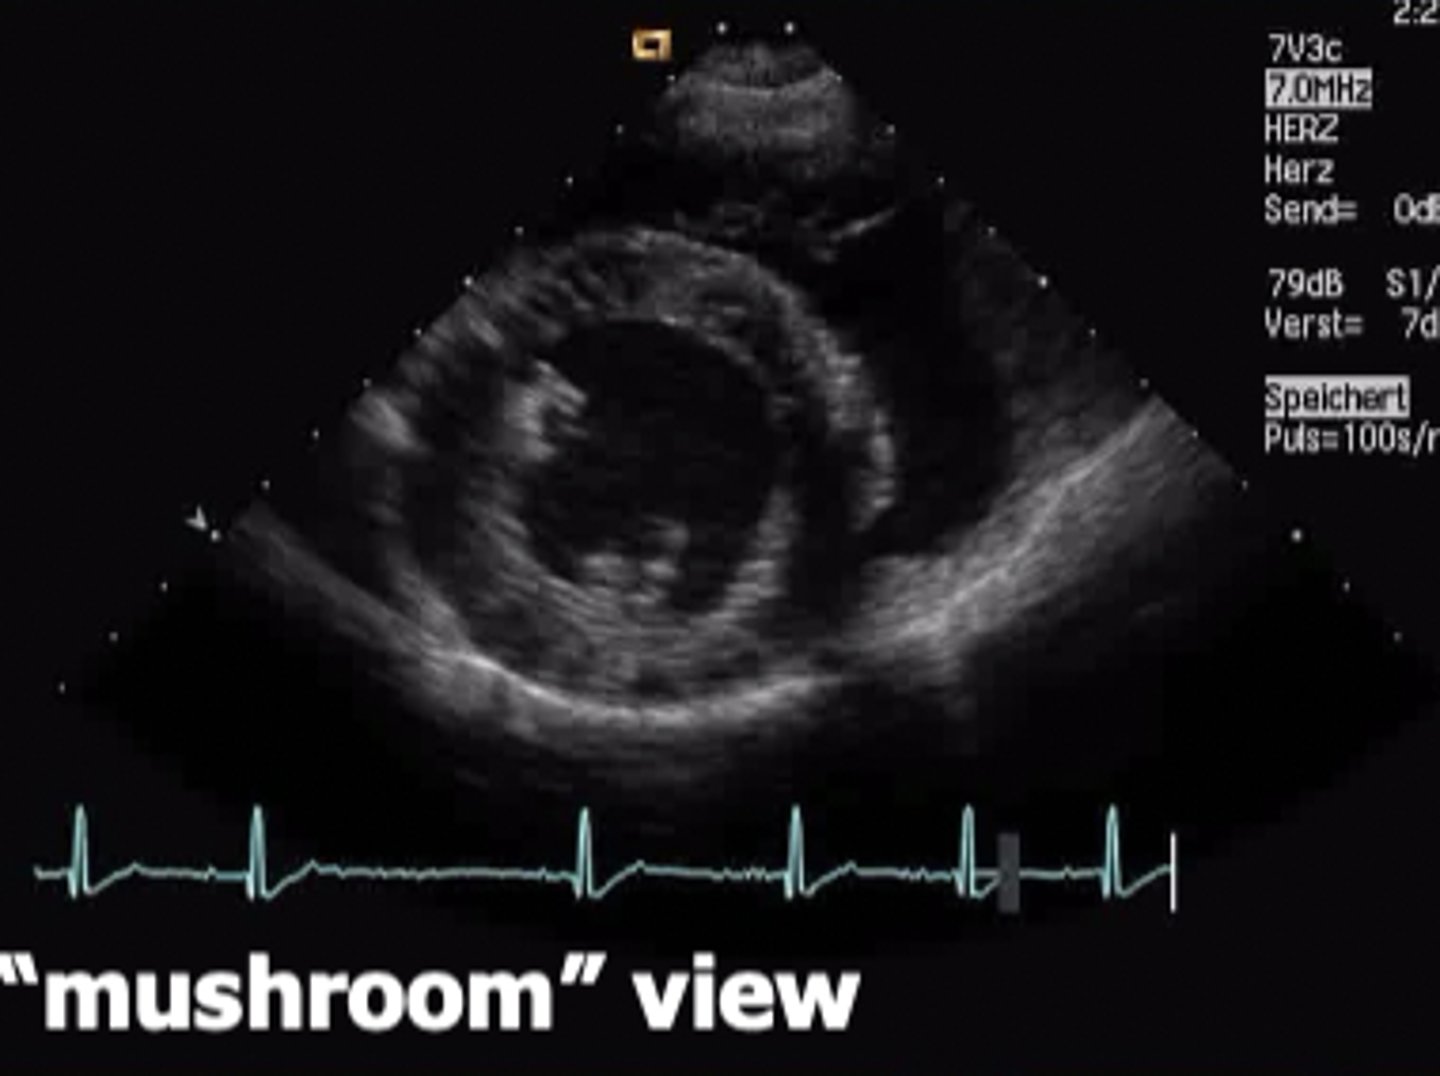

right parasternal short axis view

view that slices the heart in different crossections at several different levels (from apex to base)

What does the parasternal short axis view look like at the level of papillary muscle?

mushroom